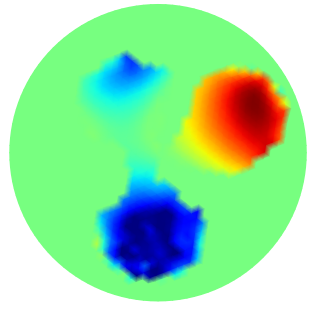

| GT | PGM-TV- | PGM-TV | |

|---|---|---|---|

|

|

|

|

| FN=0.0 % | PSNR=26.10 | PSNR=25.21 | |

|

|

|

|

| FN=0.62 % | PSNR=23.1918 | PSNR=23.044 | |

|

|

|

|

| FN=0.0 % | PSNR=26.999 | PSNR=24.6806 |

We finally evaluate the robustness against measurements corrupted by additive noise. The measured voltage is computed by the forward model KTCFwd and recorded as a vector . According to the degradation model (1), the noiseless measures are corrupted by additive white Gaussian noise to simulate experimentally measured voltages, with noise level :

| (47) |

The Signal to Noise Ratio (SNR) in dB is calculated as , while Peak-SNR (PSNR) will be used to measure the quality of an image after the reconstruction.

In Fig.5 some conductivity reconstructions are illustrated. The collected voltage has been corrupted by adding a realization of random noise with Gaussian distribution and noise level (added noise is such that the intrinsic SNR is 40dB). We observe that, even though the Oracle-Net was trained on noiseless data, the mask obtained in inference with noise measurements - Fig.5 first column - is sufficiently accurate, and PGM algorithm performs very well on the noise measurements. A natural consequence of having noise-corrupted measurements is the degradation in the conductivity reconstruction. Comparing the results in the third columns of Fig.4 and Fig.5 we observe quantitatively a degradation in the performance of reconstructions in terms of PSNR values. Analogous behavior can be observed comparing the fourth columns of Fig. 4 and Fig. 5, which have been obtained without taking advantage of the contribution of the Oracle Mask.